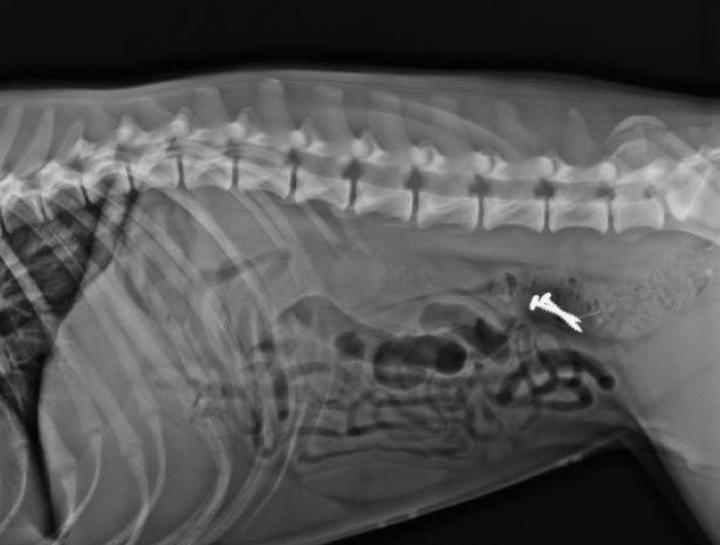

Pet Digital Radiology

Digital x-rays assist in diagnosing illness & injury.